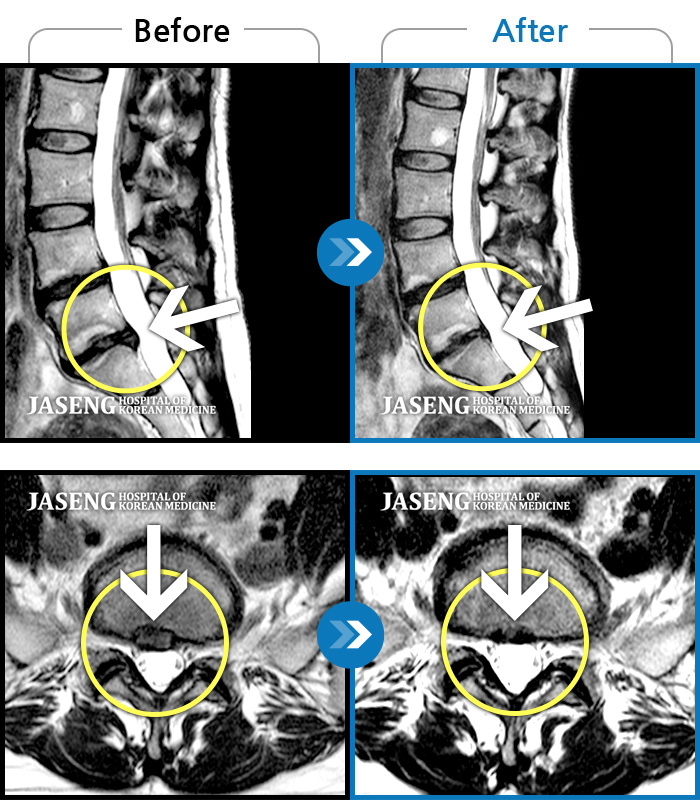

허리디스크

강남 · 강만호 원장

허리통증이 심해서 숙이기 어렵고 차에서 내리기 힘들었습니다.

촬영시기

2021.01.06 ~ 2025.03.10